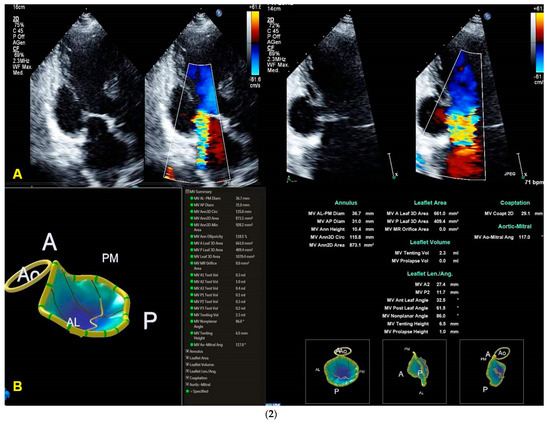

3.2. Quantification of the Morphology